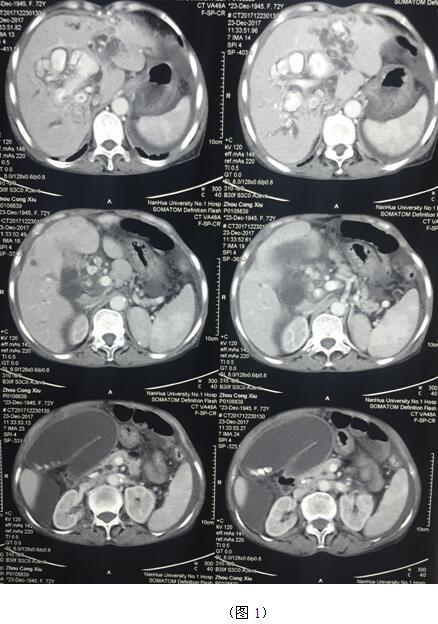

肝膽管結石疾病往往“鐘愛”貧困落后地區(qū)的病人,70多歲的周奶奶患全肝結石多年,由于家庭困難一直沒有得到有效治療,這個月病情惡化出現(xiàn)化膿性膽管炎并肝功能衰竭(圖1)。轉輾衡陽市內多家醫(yī)院,不是因高昂的治療費用止步于院外,就是被以“病入膏肓”為由推脫出院。家屬經過多方打聽得知衡陽市中心醫(yī)院是市里面的仁濟醫(yī)院,肝膽外科還是省級重點專科,家屬及病人懷著最后的希望來到了醫(yī)院肝膽外科。